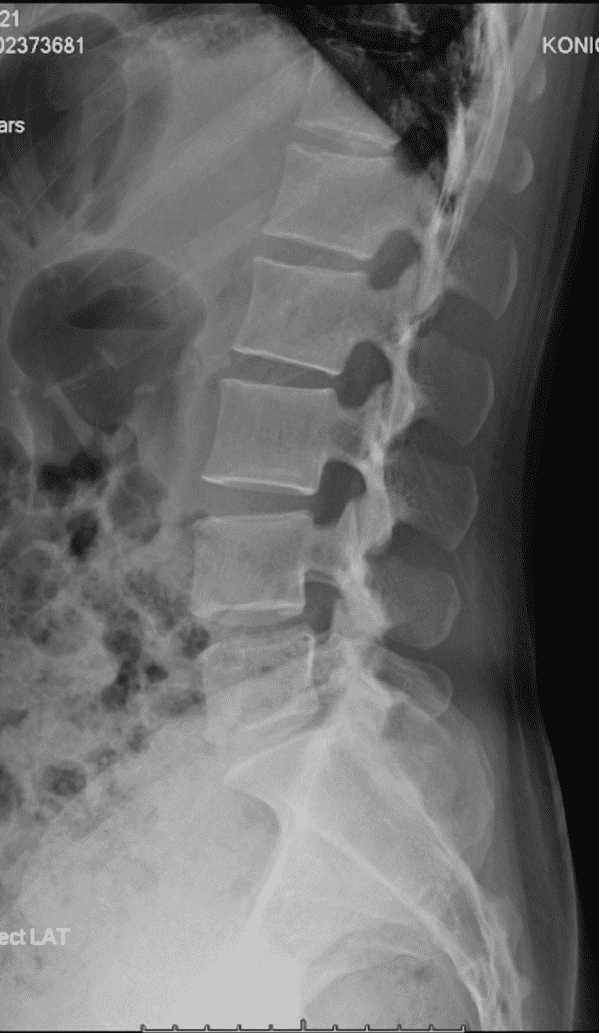

椎骨 / 髂骨 精确标记例

将传统通过点标记训练的 UNet 峰值 22 通道分类模型 + UNet ROI 窗口粗分割模型 替换为对线性顺序和先验顺序更精确的 HRNet 模型,识别率提高并且对于复杂情况的识别能力大幅提升。

将 UNet 训练的髂脊线识别模型(UNet 只适合进行分割,对于线段识别定位预测为概率热图,并不方便进行线段化)替换为 VGG16-BN 专注于线段提取。